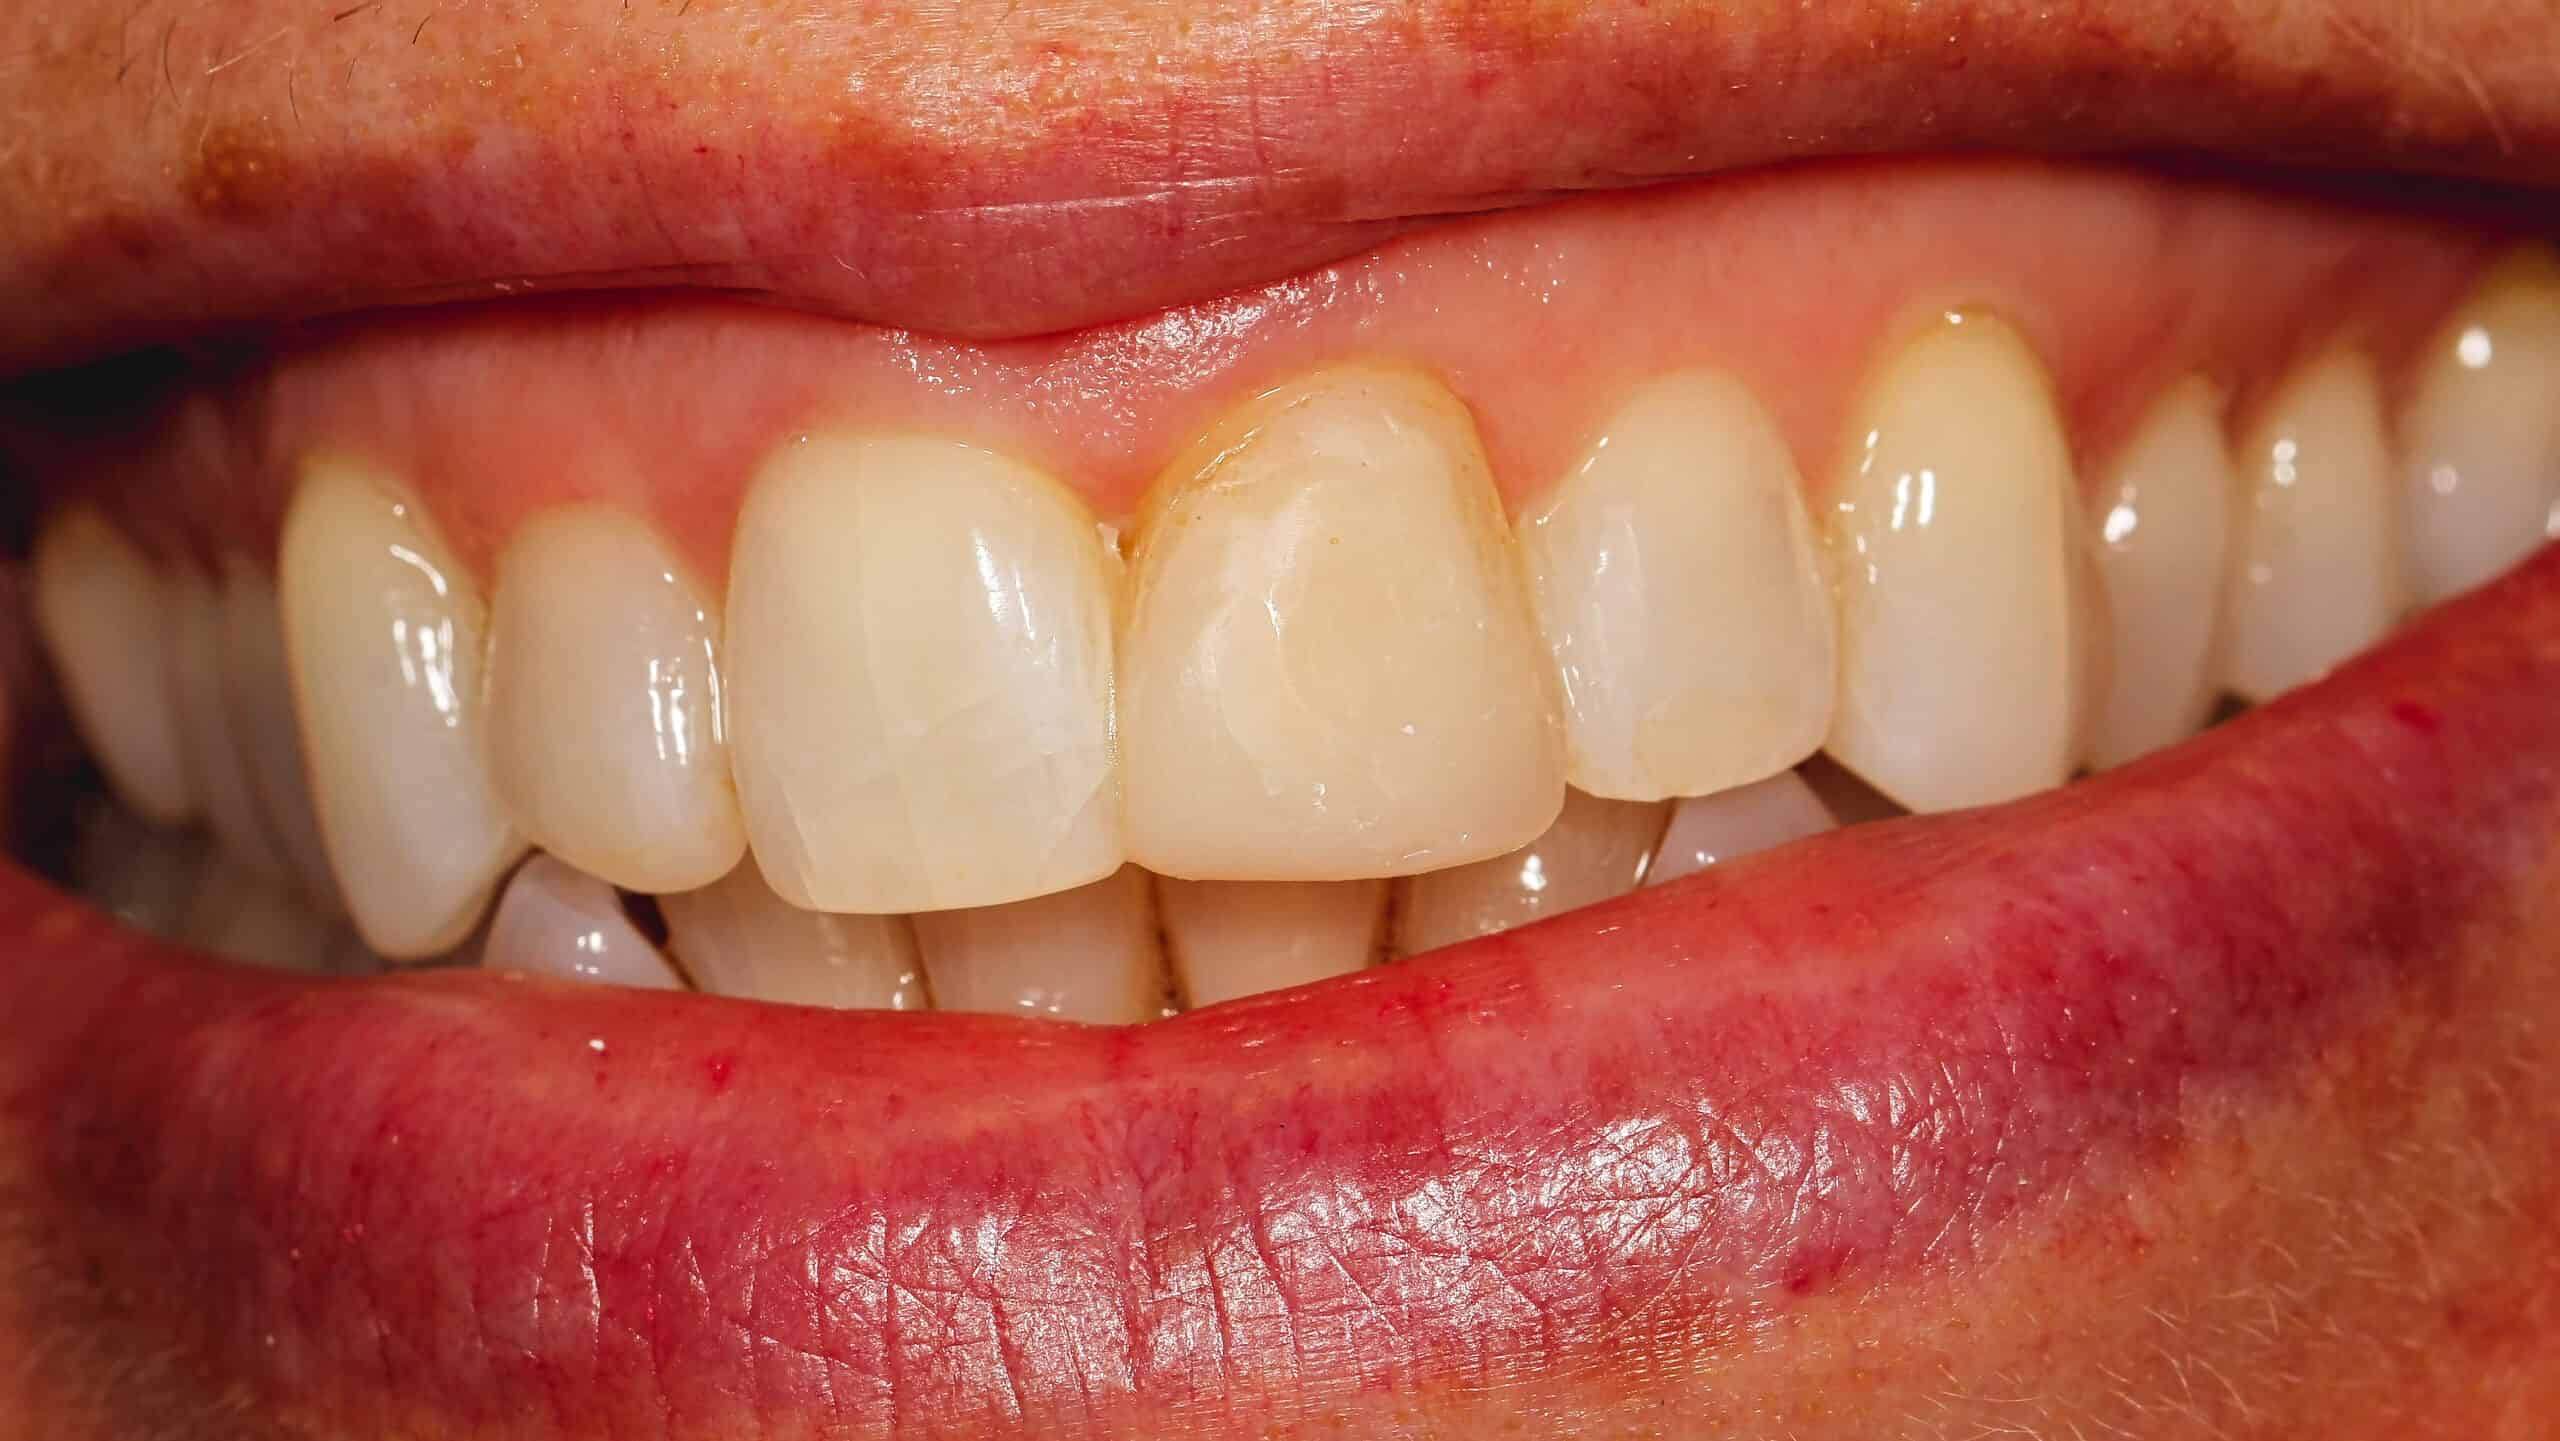

12 year old male patient fell of his bicycle on a Saturday. He hit his lip and front teeth on the pavement. He did not have much tooth pain after the initial trauma. He presented the next day to our office to evaluate the tooth for repair. As an emergency dentist in NYC we treat all types of tooth injuries.

Luckily, his front tooth did not suffer any nerve damage. The tooth was not mobile and mostly intact aside from the obvious fracture. The nerve in the tooth is was healthy, not causing any significant pain.

Since the front tooth did not sustain any nerve damage it was safe to proceed with restoring the tooth with a bonding. A bonding is the same material we often use in dental fillings. We usually do not place porcelain veneers or crowns on patients under 17 years old. Since, young patients’ bone is still growing, the crown may not look correct a few years after placement.

In this case we decided to restore the tooth with dental bonding or filling material. The procedure was performed chair-side in our office with a bit of anesthesia since the tooth was still sensitive from the trauma that it suffered. Patient left our office very happy.